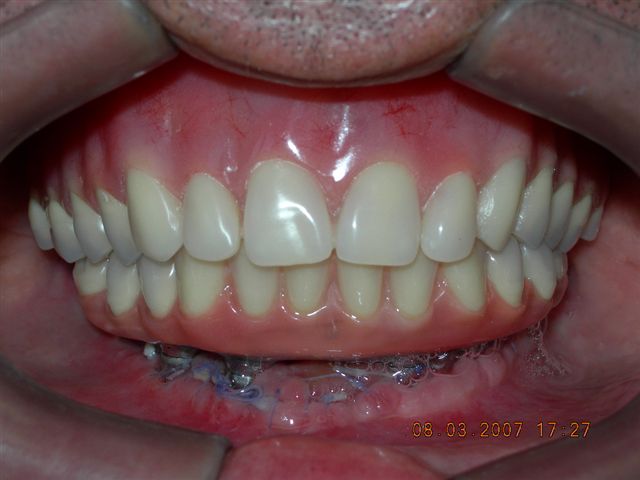

Prova de articulação pós acrilização (fase laboratorial) |

Prova de articulação após acabamento (fase laboratorial) |